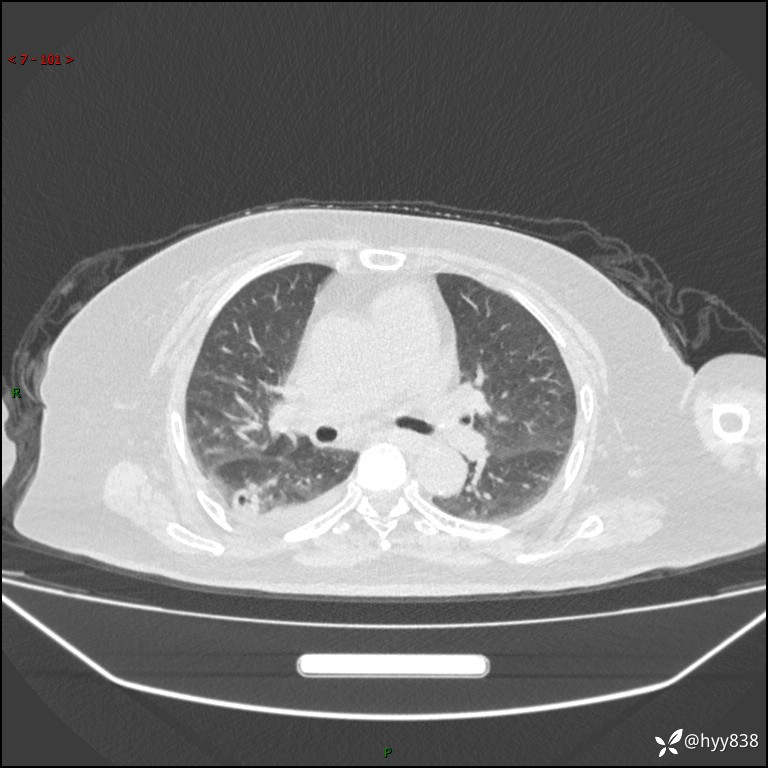

胸部 CT平扫、